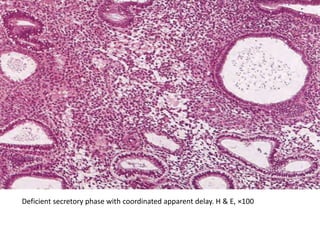

• In deficient secretory phase with coordinated apparent delay , the

functional disturbance is preceded by a persistent follicle with

irregular proliferation and late ovulation; the secretory changes that

are induced by ovulation are therefore only apparently delayed, not

delayed in relation to the day of ovulation.

• Part of the glands are cystically dilated, others narrow and only

occasionally slightly convoluted.

• The glandular epithelium shows the beginning of secretion with

basal glycogen vacuoles and slightly rounded nuclei corresponding

to the second day after ovulation in a normal secretory phase.

• The stromal cells are spindle shaped or large and separated by

focal edema.

• Spiral arterioles are present and only underdeveloped focally.

Deficient secretory phase with coordinated apparent delay.

Deficient secretory phase with coordinated apparent delay. H & E, ×100